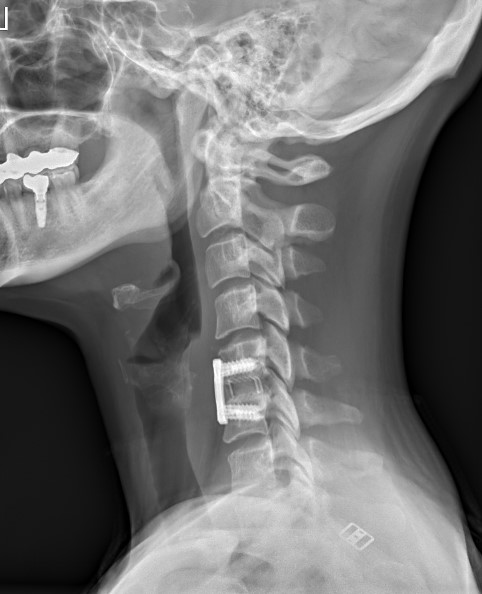

Krční páteř

Krční páteř operujeme nejčastěji z předního přístupu. Příčným řezem v tzv čárách štěpitelnosti kůže (vráskách) se dostaneme k postiženému segmentu páteře. Po odstranění meziobratlové ploténky a osteofytů, které utlačovaly nervové struktury nahradíme vyplníme meziobratlový prostor implantátem vyplněným kostním štěpem odebraným z lopaty kosti kyčelní a obratlová těla fixujeme speciální krční dlahou.

V případech víceetážového postižení krční páteře volíme operační přístup zadní.